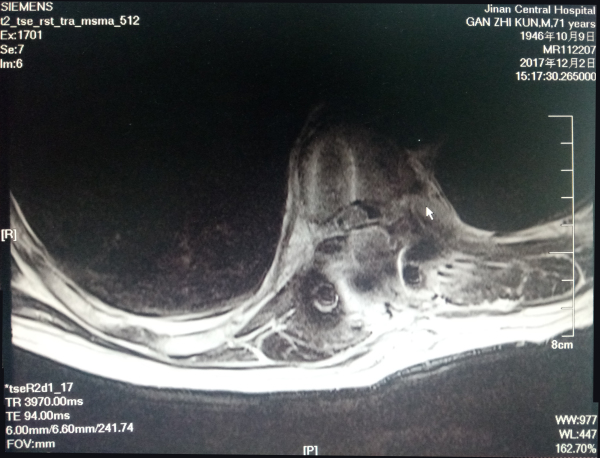

患者甘某某,男,71岁,腰痛伴双下肢麻木,皮肤感觉异常1年余,一年前无明显诱因出现腰痛,双下肢麻木,常于休息时减轻活动后加重,近日出现大小便功能障碍。患者之前曾到省内多家医院就诊,长期以“椎间盘突出症”进行治疗,效果差,近日慕名来我院就诊。脊柱外科龚维明主任医师经过细致认真的查体,并行MRI检查后,发现T9-T10水平椎管内占位,认为这是一个典型的椎管内占位患者,已出现脊髓受压症状,随着肿瘤增大,可能进一步压迫脊髓致完全瘫痪,应尽快手术治疗。

术前1

术前2